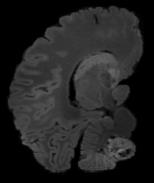

In neuroimaging, MRI tissue properties characterize underlying neurobiology, provide quantitative biomarkers for neurological disease detection and analysis, and can be used to synthesize arbitrary MRI contrasts. Estimating tissue properties from a single scan session using a protocol available on all clinical scanners promises to reduce scan time and cost, enable quantitative analysis in routine clinical scans and provide scan-independent biomarkers of disease. However, existing tissue properties estimation methods - most often $\mathbf{T_1}$ relaxation, $\mathbf{T_2^*}$ relaxation, and proton density ($\mathbf{PD}$) - require data from multiple scan sessions and cannot estimate all properties from a single clinically available MRI protocol such as the multiecho MRI scan. In addition, the widespread use of non-standard acquisition parameters across clinical imaging sites require estimation methods that can generalize across varying scanner parameters. However, existing learning methods are acquisition protocol specific and cannot estimate from heterogenous clinical data from different imaging sites. In this work we propose an unsupervised deep-learning strategy that employs MRI physics to estimate all three tissue properties from a single multiecho MRI scan session, and generalizes across varying acquisition parameters. The proposed strategy optimizes accurate synthesis of new MRI contrasts from estimated latent tissue properties, enabling unsupervised training, we also employ random acquisition parameters during training to achieve acquisition generalization. We provide the first demonstration of estimating all tissue properties from a single multiecho scan session. We demonstrate improved accuracy and generalizability for tissue property estimation and MRI synthesis.